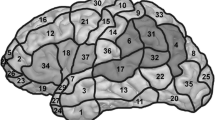

Stimulated points

We determined 46 cortical spots on the left hemisphere, which were tagged on the 3D MRI prior to each mapping session (Fig. 1). The spots were easy to reproduce in the cortical 3D reconstruction of healthy volunteers and spared areas in which stimulation would cause unacceptable pain (orbital part of the inferior frontal gyrus (orIFG), polar superior and polar middle temporal gyrus (polSTG, polMTG), anterior middle temporal gyrus (aMTG), and polar superior (polSFG), polar middle (polMFG) and polar inferior frontal gyrus (polIFG). Because of the increasing distance between skin and brain in the inferior temporal gyrus (ITG) and the consecutive decreasing stimulation intensity below 50 V/m, this region was also not mapped (Krieg et al. 2013b). Each of the 46 spots was stimulated three times per language task, thus we applied 138 stimulations per task. Thereby, the coil was placed in a strictly anterior-posterior field orientation tangentially to the skull (Epstein et al. 1996; Lioumis et al. 2012; Wassermann et al. 1999). We accepted minimum field strength of 55 V/m at the region of interest; across subjects, the field strength raged from 55 to 80 V/m.

The localization of language-positive points was described by Corina et al.’s cortical parcellation system (CPS) (Corina et al. 2005).